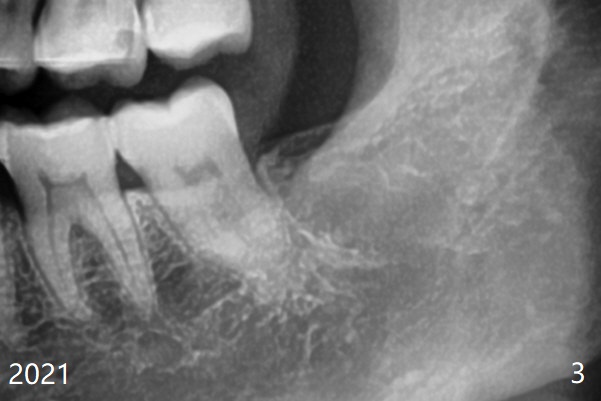

术后2年2个月#32牙槽窝密度高于#17(术后至少13年,图三)。